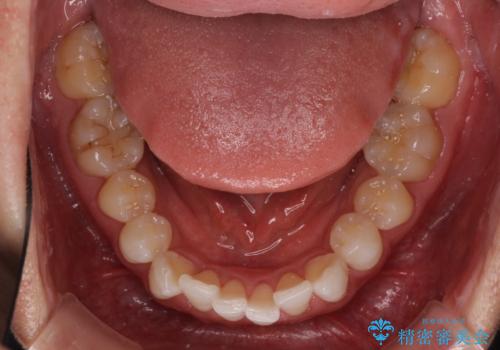

- 前歯のデコボコを治したいとのことで来院された患者様です。

上下顎ともに歯列全体の後方移動とIPR(歯と歯の間を削る)によってデコボコが解消するように設計し、インビザラインにより治療を行うこととしました。